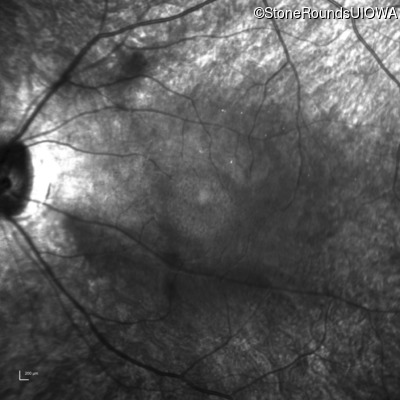

Infrared Fundus Photograph - Right - 20/60

Exemplar